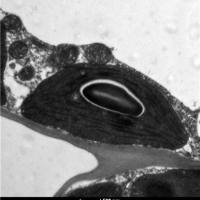

文献和实验一、石蜡切片和冰冻切片的比较? 1、要求做冰冻切片的不一定能做石蜡切片,这是我向一老师请教得出的结论。因为作石蜡切片时要高温烤片,可能会破坏组织的抗原性,如果组织的抗原性较稳定,则可作石蜡切片;但是要求做石蜡切片的,可作冰冻切片。 2、冰冻切片的优点是能够较好的保存组织的抗原免疫活性,做免疫组化时不需抗原修复这一步。缺点是细胞内易形成冰晶而破坏细胞结构,可能会使抗原弥散;切片厚度较石蜡的厚,做的片子没石蜡的漂亮。当你买一抗时,目录上都写着做什么样的切片,如果它写着只能做冰冻,就不能做石蜡,如写